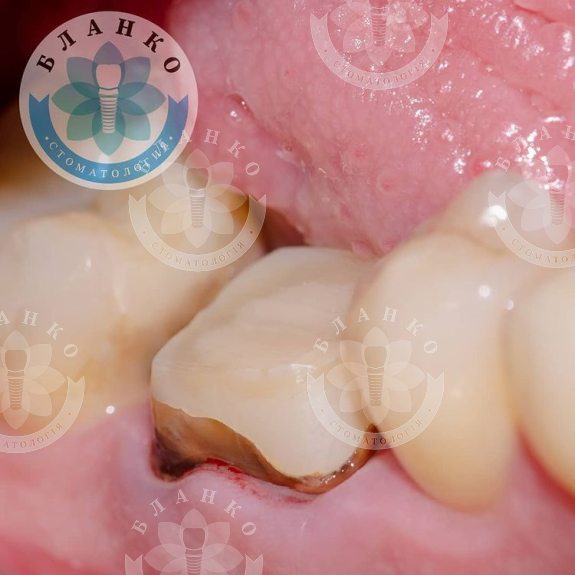

✳️На начальном снимке мы видим зуб 4.6 ( обведен красным цветом ),в котором наблюдается хроническое воспаление вокруг корней зуба и плохая реставрация из пломбировочного материала, которая давно отошла от тканей зуба и под которой развился вторичный кариес ( снимок №2 ).

— убрана несостоятельная реставрация

— извлечены анкерные штифты